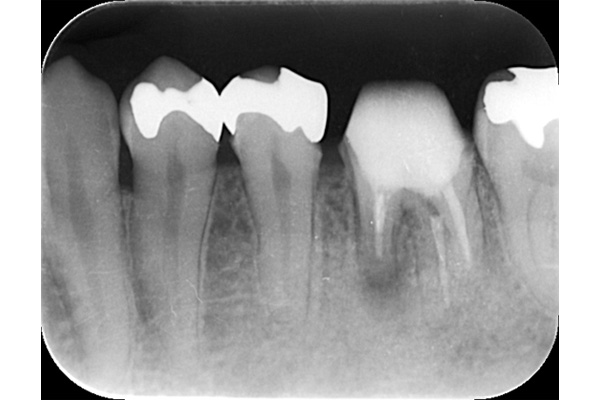

左のレントゲンでは破折したかどうかはわからないが、虫歯になっている部分をとっていくと歯が割れているのがはっきりとわかりました。

歯が割れるケースで多いのが金属の土台(メタルコア)が入っている場合です。特に根の中に長いものが入っていると、歯を割る力が強くかかるため、割れることが多いです。

こちらの写真は違和感があるということでレントゲンを撮ったが異常は見つからなかった。しかし、1ヶ月後にもう一度撮影すると、歯が割れているのがわかりました。また、歯の周りの骨の部分がやや黒くなっているのも分かります。